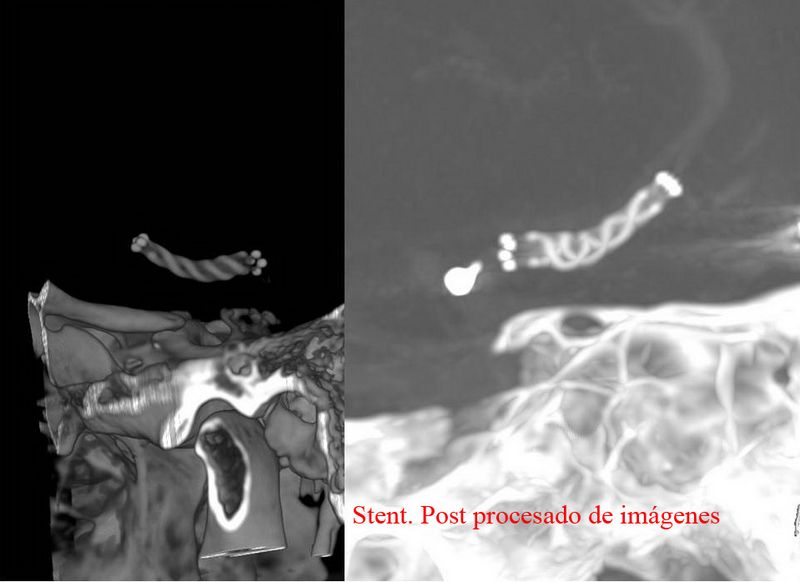

Aneurisma de arteria comunicante anterior